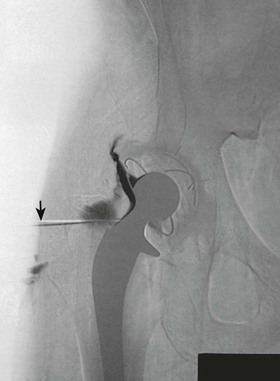

Hip arthrography is most often performed on children in a surgery suite by an orthopedic surgeon. Arthrography is used to evaluate lateral femoral head displacement and after closed reduction to ensure that there is no folding or impingement of soft tissues (see Fig. 12-2, pretreatment) (Figs. 12-14 and 12-15, post-treatment). In adults, the primary use of hip arthrography is to detect a loose hip prosthesis or to confirm the presence of infection. The cement used to fasten hip prosthesis components has barium sulfate added to make the cement and the cement-bone interface radiographically visible (Fig. 12-16). Although the addition of barium sulfate to cement is helpful in confirming proper seating of the prosthesis, it makes evaluation of the same joint by arthrography difficult.

Because cement and contrast material produce the same approximate radiographic brightness, a subtraction technique is recommended—either photographic subtraction, as shown in Figs. 12-17 and 12-18, or digital subtraction, as shown in Figs. 12-19 and 12-20 (see Chapter 23). A common puncture site for hip arthrography is

inch (1.9 cm) distal to the inguinal crease and

inch (1.9 cm) lateral to the palpated femoral pulse. A spinal needle is useful for reaching the joint capsule.